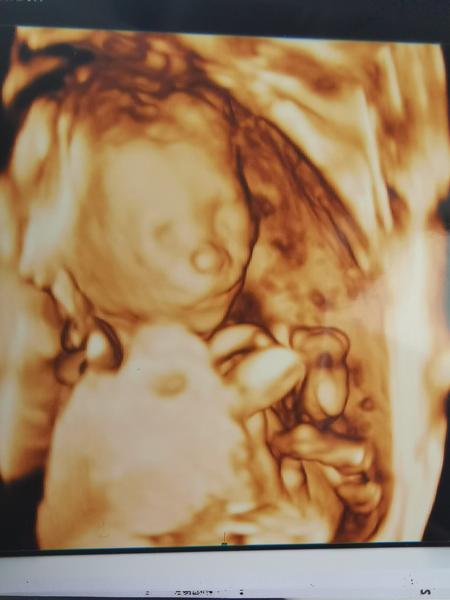

Je to holčička nebo chlapeček? Foto ultrazvuku

Ahoj maminky a budoucí maminky 😉 Prosím, poradila byste mi některá, co vidíte na fotce z ultrazvuku ve 20. týdnu za pohlaví? Určitě jste foteček viděly už mraky, proto vás žádám o radu...Nechci nikoho ovlivnit, proto svůj tip řeknu později 🙂 Děkuju moc!!!

@juliemichal Ty už plánuješ páté kolo😂. Teď v předposledním dílu pořadu Malé lásky se měl taky narodit několikrát potvrzený chlapeček a narodila se holčička 😄. Já už toto těhotenství prožívám těžce a už nechci 😂. Doktor u mě na 3d nakonec řekl chlapeček taky, ale byl to boj 😲. Ještě jdu na velký ultrazvuk a pořád doufám že se pletou 😁

@pavlinkadv Ta moje fotka je z 21. týdne a pohlaví tam je 😉